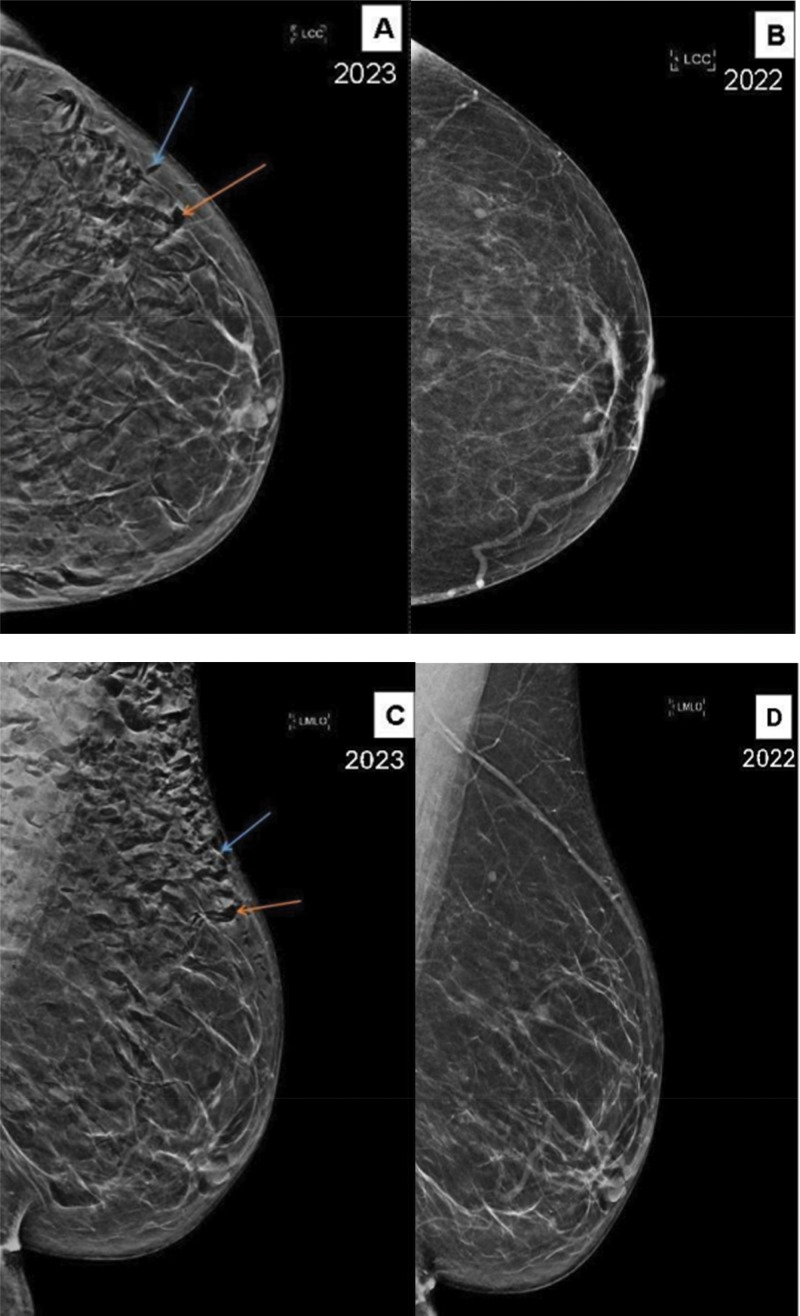

教学要点:乳房肿是一种罕见但良性的乳房x线检查结果,通常与近期的仪器检查有关。通常,它不需要进一步的检查,尽管当发现足够广泛以掩盖小病变或微钙化时可能需要重复成像。

Teaching point: Pneumomastia is a rare but benign mammographic finding most often related to recent instrumentation. Typically, it does not require further workup, although it may necessitate repeat imaging when the finding is extensive enough to obscure small lesions or microcalcifications.